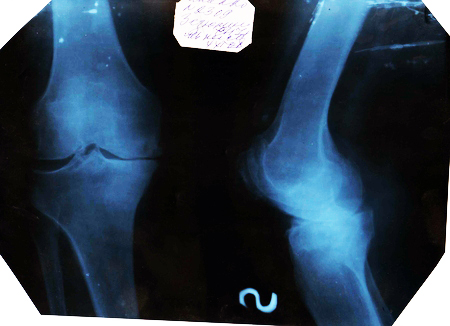

Помогите обработать фотоМне в понедельник презентацию показывать на конференции, а научный руководитель забраковал отсканированные рентгеновские снимки, сказал темно и надо осветлить в фотошопе, а У МЕНЯ ЕГО И НЕТ .....И НЕ РАЗБИРАЮСЬ В НЕМ!!!!!!!!!!!!!!!

Это остеоартроз???

По боковому снимку - совсем гибло!

Да. Анют, да тм уже последняя стадия)))) Это я преентацию для студентов делала. Буду защищаться по терапии, тема коморбидная патология артериальная гипертензия и остеоартроз, но в будущем не исключаю и ревматолога)))

а вроде как и целые кости,не вижу патологии...если не секрет-на какую тему презентация?

Остеоартроз))))))) Это уже запущенная стадия, сустав практически обездвижен

Хм...недавно повредила мениск(на велике гоняла)))),делали снимок-один в один....и суставная щель такая же и вообще...боковая проекция только может чуть отличается....приятно пошевелить декретными мозгами)))))